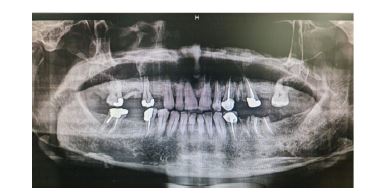

گزارش مورد : بیمار مردی ۵۷ ساله، بدون سابقه بیماری سیستمیک خاص، با شکایت تورم مزمن، بدون درد و با رشد آهسته در ناحیه قدامی ماگزیلا از 1سال گذشته در اسفندماه 1402 به درمانگاه دندانپزشکی مراجعه کرده و پس از بیوپسی و شک به OKC بیمار توسط دندانپزشک به سرویس جراحی دهان و فک و صورت بیمارستان شهید رهنمون یزد ارجاع داده شد. تورم طی یک سال گذشته بهتدریج افزایش یافته بود و با مصرف دارو یا اقدامات دندانی پیشین بهبود نیافته بود. بیمار سابقه ضربه یا جراحی قبلی در این ناحیه نداشت. در معاینه خارجدهانی، تورم غیرقرینه در ناحیه زیر بینی و لب فوقانی مشاهده شد که موجب برهمخوردن خفیف تقارن صورت شده بود. پوست روی ناحیه متورم طبیعی و فاقد تغییر رنگ یا زخم بود (شکل 1و2) (نمای تحتانی صورت نیز برجستگی پایه بینی و ناحیه سابنازال را تأیید کرد. در معاینه داخلدهانی، تورم سفت و بدون درد در مخاط لبی ماگزیلا از ناحیه مولر دوم سمت راست تا مولر دوم سمت چپ دیده شد. مخاط روی ضایعه اندکی قرمزتر از مخاط مجاور بود، ولی زخم، ترشح یا التهاب حاد مشاهده نشد (شکل 3). رادیوگرافی پانورامیک اولیه، ضایعهای رادیولوسنت، تکحفرهای و با حدود مشخص را در ناحیه قدام وخلف ماگزیلا نشان داد که از دندان مولردوم سمت راست تا مولر دوم سمت چپ امتداد داشت و منجر به نازکشدگی قابلتوجه کورتکس قدامی شده بود (شکل ۴). ارزیابی تکمیلی باCBCT، ضایعهای با گسترش وسیع (2*3*4 سانتیمتر) در محور قدامی-خلفی فک بالا را تأیید کرد که بدون درگیری سینوس فکی یا کف بینی بود. دیوارههای استخوانی پالاتال و باکال در محل ضایعه نازک شده اما پیوسته بودند. جابهجایی اندک ریشههای دندانهای مجاور بدون تحلیل ریشه مشاهده شد (شکل 5). با توجه به ویژگیهای بالینی و تصویربرداری، تشخیصهای افتراقی شامل آملوبلاستوما، کیست مجرای نازوپالاتین و OKC مطرح شد. بیوپسی انسیزیونی از ضایعه انجام و نمونه جهت بررسی هیستوپاتولوژیک ارسال شد. گزارش پاتولوژی نشان داد که ضایعه دارای اپیتلیوم سنگفرشی مطبق پاراکراتینیزه با سطح مواج و چینخورده، بدون رتپگ، و لایه بازال نردبانی با سلولهای استوانهای پلاریزه است. کراتین فراوان در لومن مشاهده شد و میتوز در لایههای بازال و پارابازال وجود داشت. این ویژگیها با تشخیص OKC نوع پاراکراتینیزه مطابقت داشتند (شکل 7). با توجه به محل ضایعه، اندازه نسبتاً بزرگ آن، و نزدیکی به ساختارهای حیاتی مانند حفره بینی و قاعده سینوس، تصمیم به انجام درمان مرحلهای گرفته شد. در مرحله اول، مارسوپیالیزاسیون تحت بیهوشی عمومی با اینتوباسیون نازال انجام شد. برش وستیبولار دوطرفه در قدام ماگزیلا ایجاد و پس از بازکردن دیواره کیست، دو عدد درن نلاتون در طرفین ضایعه قرار داده شد. بخیه لبههای مخاطی به دیواره کیست با نخ سلیک ۰-۲ انجام و مخاط با ویکریل ۰-۳ سوچور شد. شستشوی کامل با نرمالسالین انجام شد و پانسمان داخل حفره با گاز استریل صورت گرفت (شکل 8). تا زمان حضور بیمار در بیمارستان شستشو توسط پزشک انجام شد و نهایتا پس از آموزش شستشو به بیمار و اطمینان از آموزش وی بیمار مرخص گردید. در پیگیریهای انجام شده در فواصل دو هفته، یک ماه، سه ماه و شش ماه، بیمار بدون علائم عود، درد یا ترشح باقی ماند. تورم بهتدریج کاهش یافت و نمای مخاطی ناحیه به وضعیت نرمال نزدیک شد. گرافی پانورامیک پیگیری شش ماهه کاهش چشمگیر اندازه ضایعه و افزایش تراکم استخوان را نشان داد (شکل 9). با توجه به پاسخ مناسب ضایعه به مرحله اول درمان، برنامهریزی برای انجام انوکلیشن تأخیری به همراه برداشت محیطی (Peripheral Ostectomy) پس از شش ماه انجام شد. در مرحله دوم تحت بیهوشی عمومی، با ایجاد یک برش وستیبولار و نمایان شدن ناحیه ضایعه، پوشش ضایعه از دیوارههای استخوانی جدا گردید. بهمنظور برداشت استخوان مجاور پوشش کیستیک، از فرز جراحی استفاده شد. پس از انجام انوکلیشن، حفره با ژلفوم پر گردید و برشها با نخ بخیه ۴-۰ پرولن بسته شدند. هدف از این اقدام، حذف کامل اپیتلیوم باقیمانده و کاهش خطر عود ضایعه در بلندمدت خواهد بود.

شکل9: نمای پانورامیک شش ماه پس از مارسوپیالیزاسیون، نشاندهنده کاهش چشمگیر حجم ضایعه، افزایش تراکم استخوانی و عدم عود ضایعه در ناحیه قدامی ماگزیلا.